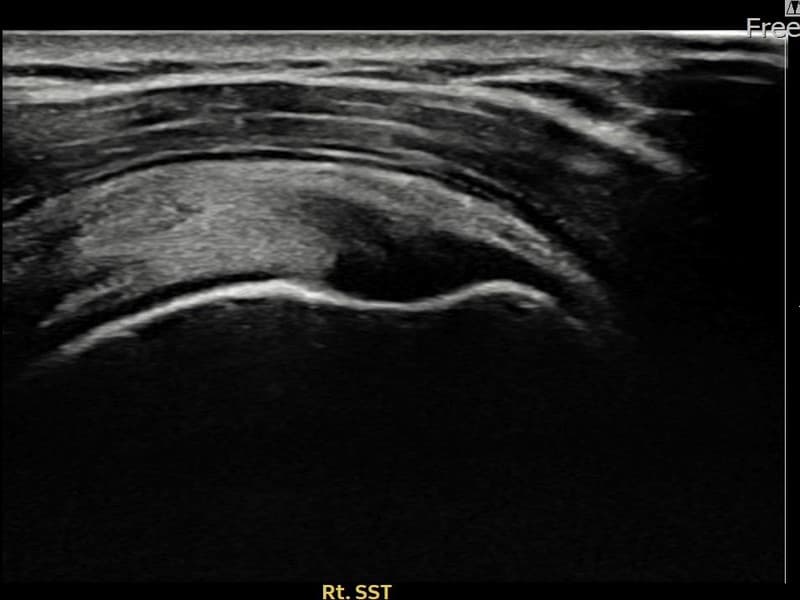

시술 전 초음파 측정 결과 파열 크기는 10mm × 4mm (힘줄 두께의 약 42% 결손)로 확인되었습니다. 시술 전 초음파에서 우측 극상근건 부착부의 에코 단절과 힘줄 결손 소견이 확인되었습니다. 시술 후 초음파에서 부착부 연속성이 회복되고 결손 부위에 재생 조직이 형성된 것이 관찰되었습니다.

50대 초반 남성 환자분으로, 오른쪽 팔을 자주 사용하는 직업 특성상 반복적인 어깨 사용으로 부분파열이 진행되신 분이었습니다. 어깨 외측 통증이 수개월째 지속되고 팔을 들어 올릴 때마다 날카로운 통증이 있어 일상 활동에 큰 불편함이 있으셨습니다. 초음파 검사에서 극상근건 부착부 부분파열이 확인되었으며, 초음파 유도 하 축소봉합술을 시행하였습니다. 시술 후 단계적 재활 운동을 통해 회복을 진행하였고, 시술 13주 후 추적 초음파에서 부착부 힘줄 연속성이 완전히 회복된 것이 확인되어 정상 업무에 복귀하셨습니다.